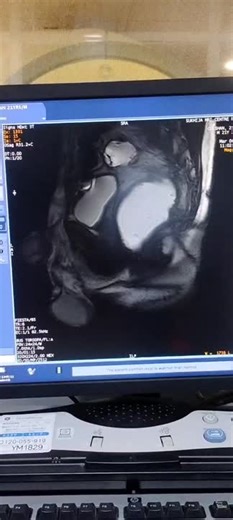

MRI DefecographyMRI Defecography is a specialized imaging test used to assess pelvic floor function and diagnose disorders affecting bowel movements. It provides detailed images of the rectum… | Manoj gill

MRI Defecography